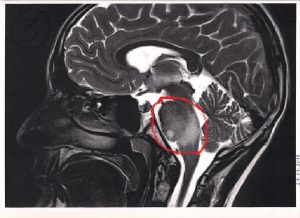

Dziś zgrywaliśmy wszystkie rezonanse na płytki i wysyłamy je do nowo powstającej kliniki w Szwajcarii. Szefowa kliniki nic nam nie obiecuje oprócz tego, że osobiście bardzo dokładnie przestudiuje rezonans. Dr Sabine Muller należy do grona najwybitniejszych specjalistów na świecie,ale pierwsze słowa jaj maila to były głębokie wyrazy współczucia, że spotkał nas właśnie ten, strasznie niebezpieczny wróg, guz pnia mózgu DIPG, od angielskiej nazwy Diffuse Intrinsic Pontine Glioma. Walka z tym nowotworem przypomina walkę z bardzo podstępnym i żywotnym smokiem, któremu potrafią odrosnąć trzy głowy w miejsce ściętej jednej. Na dodatek u każdego guz dziecka jest inny… a pień mózgu to taka jaskinia, do której nie da się wejść. Znajdują się tam wszystkie najważniejsze ośrodki naszego życia- oddychanie, przełykanie, widzenie, chodzenie.

Biopsja, czyli pobranie próbki guza, z tego powodu niesie ogromne niebezpieczeństwo uszkodzenia któregoś z tych najważniejszych nerwów a pobranie próbek często bywa mylące, ponieważ struktura guza jest niejednorodna i próbka pobrana w jednym miejscu może być zupełnie inna w innym miejscu do którego nie ma dostępu.

O wycięciu guza nie ma mowy. Jego struktura przypomina zmiksowany jogurt z truskawkami a nie da się wyciąć całej truskawki z jogurtu złożonego z cząsteczek jogurtu i truskawki, z komórek zdrowych i chorych.

Na zdjęciach widać to tak : ten z lewej najjaśniej świecący- to potwór z 25.05.2018 i takiego go zobaczyliśmy po raz pierwszy. Po naświetlaniach w zasadzie całkiem zniknął, ateraz wyłania się powoli z cienia jak zły duch…

The fight with this tumor is like fighting with a sneaky dragon. After cutting of one head he can grow three new in its place. Morover, it varies from child to child and the spot he is placed (brainstem) is like a cave to which no one can see in. Pons is the part of the brainstem where main processes of our bodily functions are performed…breathing, swallowing, seeing, walking. In many cases getting a sample of that tumor through biopsy is causing a damage to one of those important nerves, and removing the tumor surgically is impossible, its structure looks like a smoothie, and it is impossible to pick up the sick cells from it.

The photos shows: the first photo is from w got the diagnosis, the bright region is the moster we are fighting with since may last year…it almost dessapeared after radiotherapy and now is emerging from the shadows again…